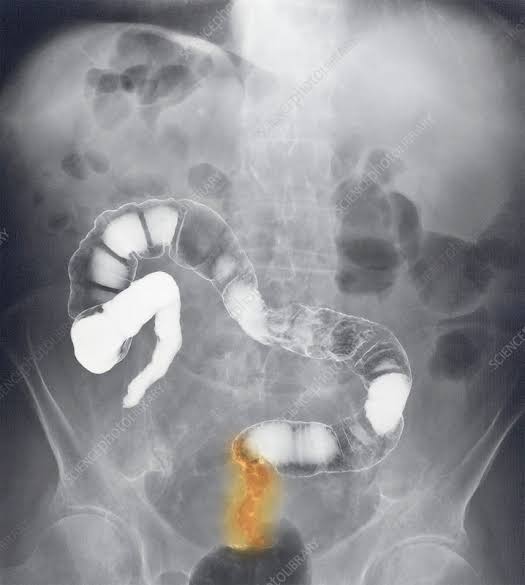

Bhargabh is only 20 years old. Just months ago, he was a healthy, gym-going young boy with big dreams. Today, he is fighting rectal cancer from a hospital bed. For the past year, his parents have done everything they could to continue his treatment. They have used their savings and sold what they had. But now, they are running out of time and resources. Doctors have warned that treatment cannot be delayed. Your contribution of ₹300, ₹500, or any amount can help continue his care. Please stand with Bhargabh today. Your support can help him fight for a new beginning.